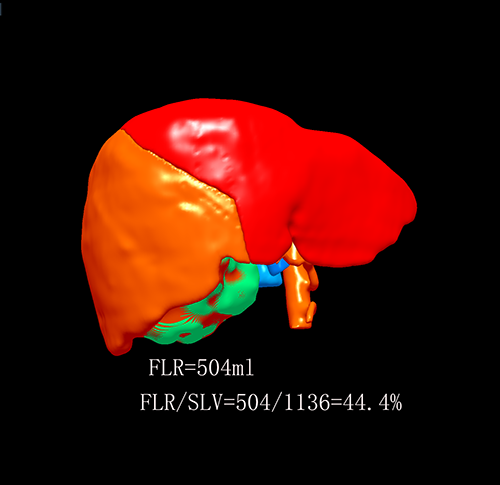

右肝癌----S567切除